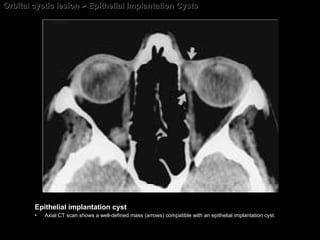

Epithelial Implantation Cysts Derived from cells of  cutaneous epithelium conjunctival epithelium or respiratory epithelium that are traumatically displaced under the skin of the eyelid or into the orbit.  The CT and MR imaging appearance; Nonspecific. Similar to that of any simple cyst.  A nonenhanced cystic orbital mass following orbital surgery or enucleation should raise the question of the presence of an epithelial implantation cyst.

Orbital cystic lesion > Epithelial Implantation Cysts Epithelial implantation cyst Axial CT scan shows a well-defined mass (arrows) compatible with an epithelial implantation cyst.